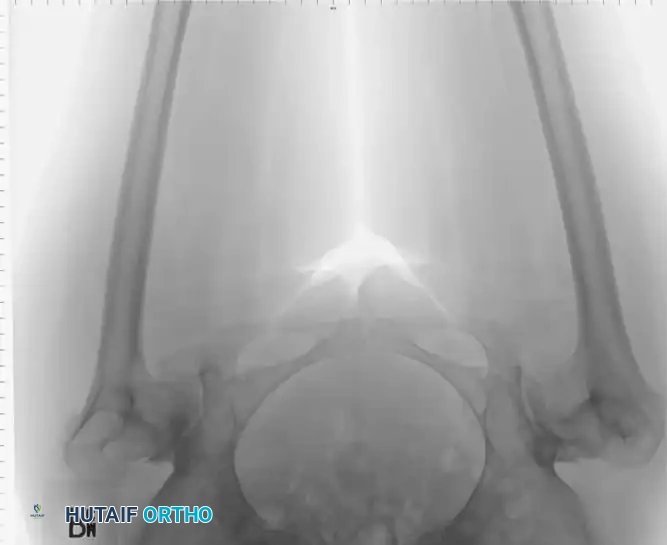

Fig. 7-74 Primary protrusio acetabuli. Otto pelvis in 52-year-old woman. Femoral head has migrated medial to ilioischial (Kohler) line. Hip motion is severely limited.

Fig. 7-75 Reconstruction for protrusio acetabuli deformity. A, Diagrammatic representation of medial wall grafting and lateralized cup placement.

Fig. 7-75 Reconstruction for protrusio acetabuli deformity. B, After total hip arthroplasty. Hip center was restored to more lateral and inferior position. Large acetabular component allowed rim fixation without need for screws, and medial deficits were grafted with cancellous autograft from femoral head with excellent incorporation.